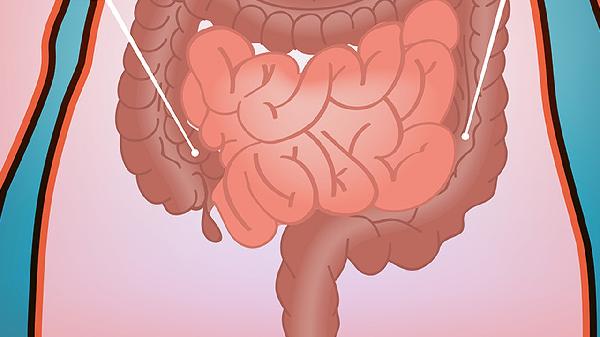

先天性腸旋轉不良主要由胚胎期腸管旋轉固定異常引起,常見原因包括中腸旋轉不全、腸系膜固定缺陷、臍帶發育異常、遺傳因素及母體環境干擾。

胚胎第6-10周中腸未完成270度逆時針旋轉,導致盲腸停留于右上腹,腸系膜根部縮短。這種解剖異常可能引發腸扭轉或十二指腸梗阻,患兒出生后常出現膽汁性嘔吐等急腹癥表現。

正常發育中腸系膜應固定于后腹壁,若固定過程受阻則形成游離腸系膜。這種缺陷使腸道活動度異常增大,約60%病例伴隨中腸扭轉風險,需通過超聲檢查腸系膜上動脈位置進行診斷。

臍腸系膜管殘留或臍疝可能機械性阻礙腸管旋轉。研究顯示臍膨出患兒合并腸旋轉不良率達30%,這類病例往往需要出生后立即評估消化道解剖結構。